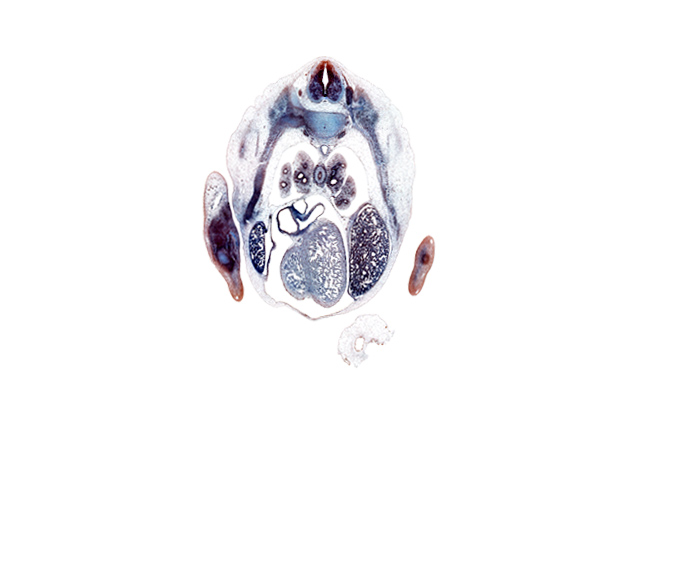

Carnegie Embryo #9325 | Location: 18-4-3

Keywords: T-5 intercostal nerve, T-5 spinal ganglion, aorta, flexor tendons in forearm, iliocostalis muscle, inferior vena cava, left lobe of liver, longissimus muscle, lower lobe of left lung, lower lobe of right lung, medial tertiary bronchus, middle lobe of right lung, oblique fissure, palmar side of hand plate, pericardial cavity, pleuropericardial membrane, pleuroperitoneal membrane, posterior basal tertiary bronchus, right atrium, right lobe of liver, semispinalis muscle, sympathetic trunk, upper lobe of left lung

Source: The Virtual Human Embryo.